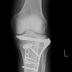

骨折後のリハビリのため、久しくのテニス、再開中です。 昨秋、プレート抜釘手術をして、全回復を目指しているのですが。これがまた…